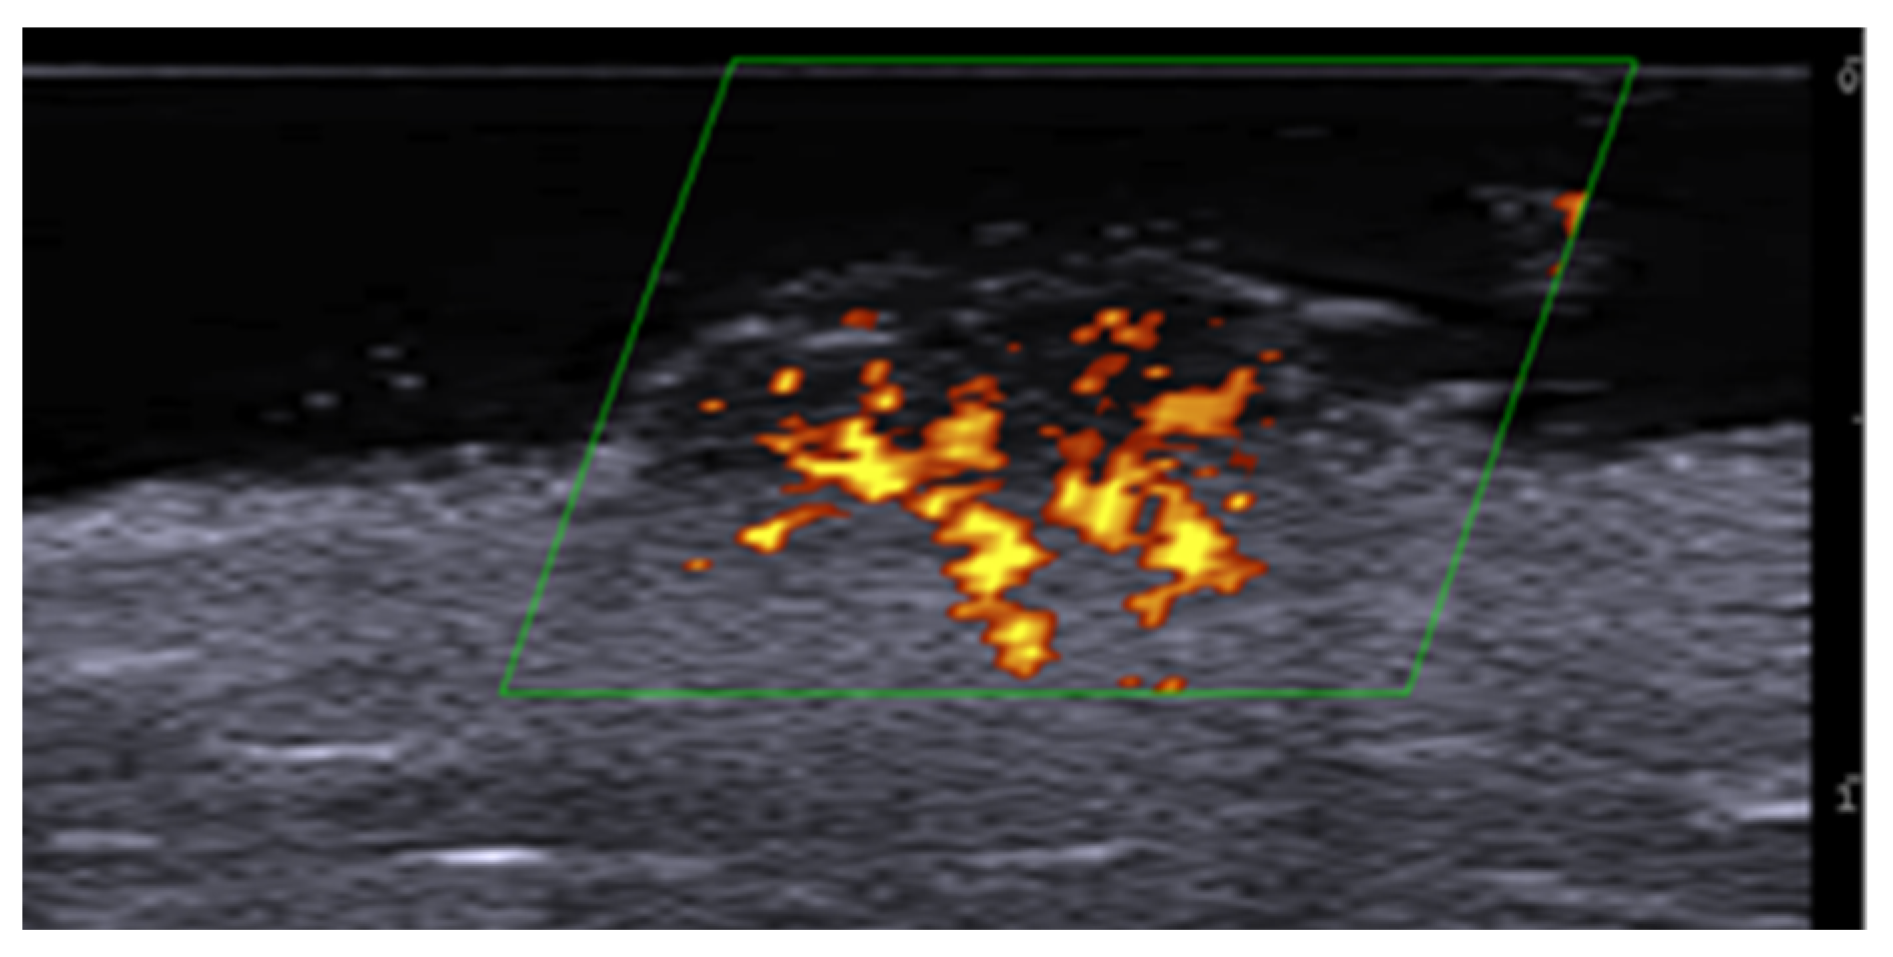

- Cataldo-Cerda, K.; Wortsman, X. Dissecting Cellulitis of the Scalp Early Diagnosed by Color Doppler Ultrasound. Int. J. Trichology 2017, 9, 147–148. [Google Scholar] [CrossRef]